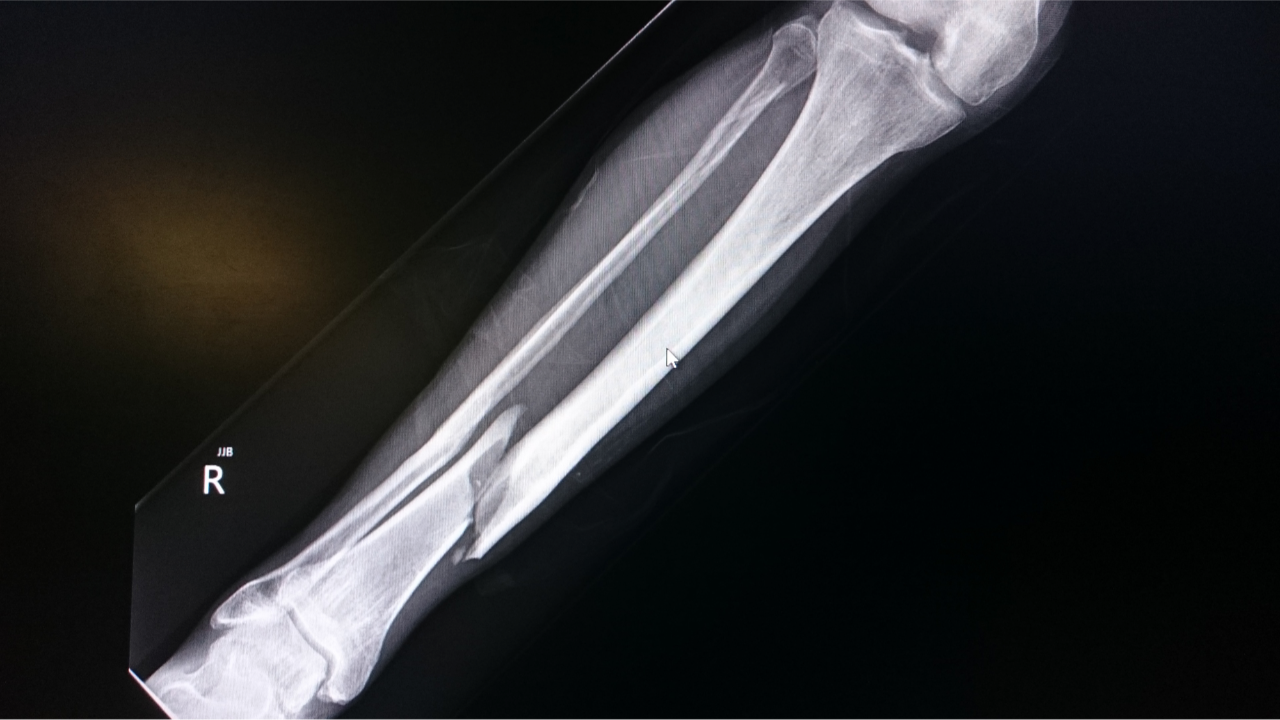

Extraspinal Trauma Patterns

Trauma DXI is not limited to the spine.

Common extraspinal topics include:

• Long bone fractures

• Joint dislocations

• Pelvic fractures

The key question is rarely “what bone is broken?”

It’s “is this injury stable, unstable, or dangerous?”